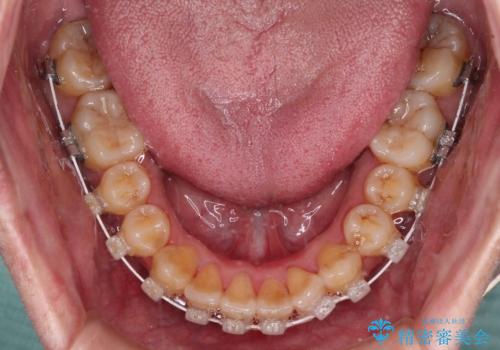

八重歯とクロスバイト 目立たないワイヤー装置で矯正治療

- 矯正装置

- 審美装置

- 八重歯と前歯のクロスバイトを改善したいとのことで来院された患者様です。

マウスピース矯正での自己管理には自信がないとのことで、ワイヤー装置による矯正治療を行うこととしました。